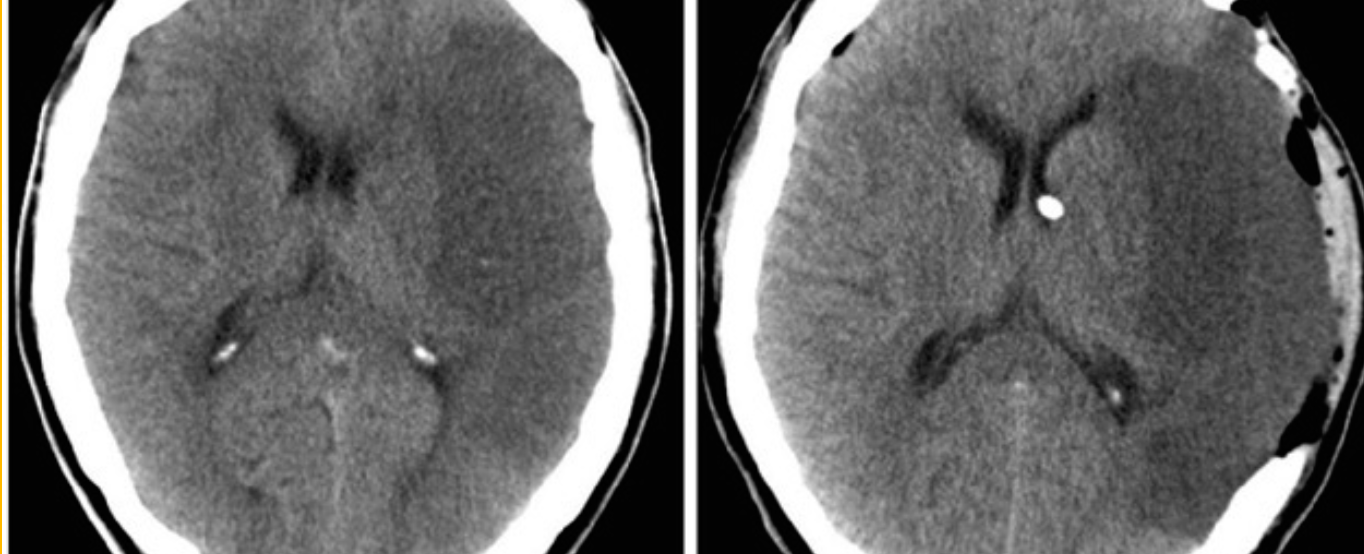

Axial CT scan obtained in a 57-year-old man who presented with left hemiplegia and obtundation.

Name the site of the lesion?

---basal ganglia---

What is commonest cause of this lesion?

---hypertension---